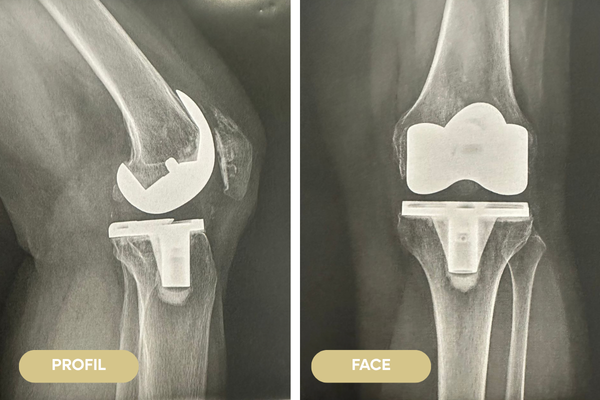

PROTHÈSE DE GENOU

La prothèse de genou est une intervention très fréquente en France (80 000).

L’opération consiste à enlever le cartilage usé et quelques millimètres d’os puis à recouvrir les surfaces osseuses du fémur et du tibia par du métal séparé par un insert en polyéthylène (plastique chirurgical) qui permet le glissement. En général la rotule sera amincie et recouverte d’un bouton en polyéthylène.

Elle permet de retrouver de la mobilité et de diminuer les douleurs dans 80% des cas.

Il existe de nombreux type de prothèses de genou, votre chirurgien choisira celle qu’il pense adaptée à votre situation.

Comment s'organise une prothèse totale de genou (PTG) ?